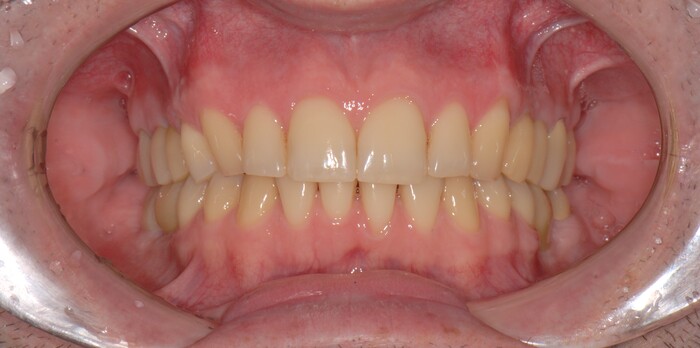

Спустя две недели произведена фиксация временных коронок.

Коронки на имплантатах на нижней челюсти:

Параллельно я удалил два центральных верхних резца, после чего были зафиксированы все остальные временные коронки.

Подчеркну - коронки временные (!), все они будут заменены на постоянные.

А как стало на промежуточном этапе:

Согласитесь, выглядит очень даже неплохо, если опустить цвет.